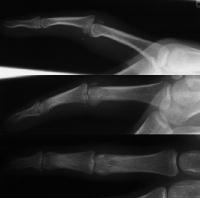

Here, the graft is in place and the joint has been reduced. The proximal two screws were then backed out slightly, and the volar plate was secured with sutures looped around the proximal two screws, which were then tightened back (not shown).

Final reconstruction.